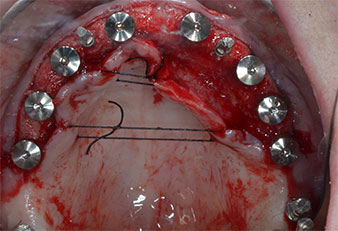

Uno strumento piezoelettrico (Piezomed I1) a forma di fiamma, rivestito in diamante, è stato usato per contrassegnare le posizioni dell'impianto e per eseguire una preparazione pilota (Fig. 3). Si è prestato attenzione a utilizzare un movimento verticale ascendente e discendente, con potenza ridotta, irrigazione completa e bassa pressione (inferiore a 300 g). Successivamente è stato applicato uno strumento pilota (Piezomed I2A/I2P) per l'ingrandimento iniziale delle sedi dell'impianto del diametro di 2 mm (Fig. 4), seguito da un inserto da 3 mm (Fig. 5).

In caso di osso denso, l'intera sequenza strumentale comprendente gli strumenti intermedi Piezomed Z25P e Z35P deve essere utilizzata per ampliare le osteotomie prima della successiva fase di allargamento.

Essi sono anche indicati per la preparazione vicino alla membrana del seno in relazione a procedure di rialzo interno o quando l'altezza ossea residua è inferiore a 4 mm.

Nel presente caso, gli strumenti Z25P e Z35P non sono stati utilizzati a causa dell'osso posteriore relativamente morbido, che è stato facilmente gestito mediante I3A/I3P.